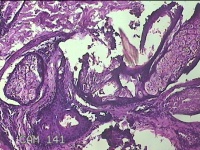

头皮包块

性别

男

年龄

34岁

临床诊断

头部脂肪瘤

一般病史

发现头皮包块2年余。考虑头部脂肪瘤

标本名称

大体所见

灰白粉红色梭形皮肤包块3x2x0.7cm一个,表面糜烂,切面灰白粉红色,质软。